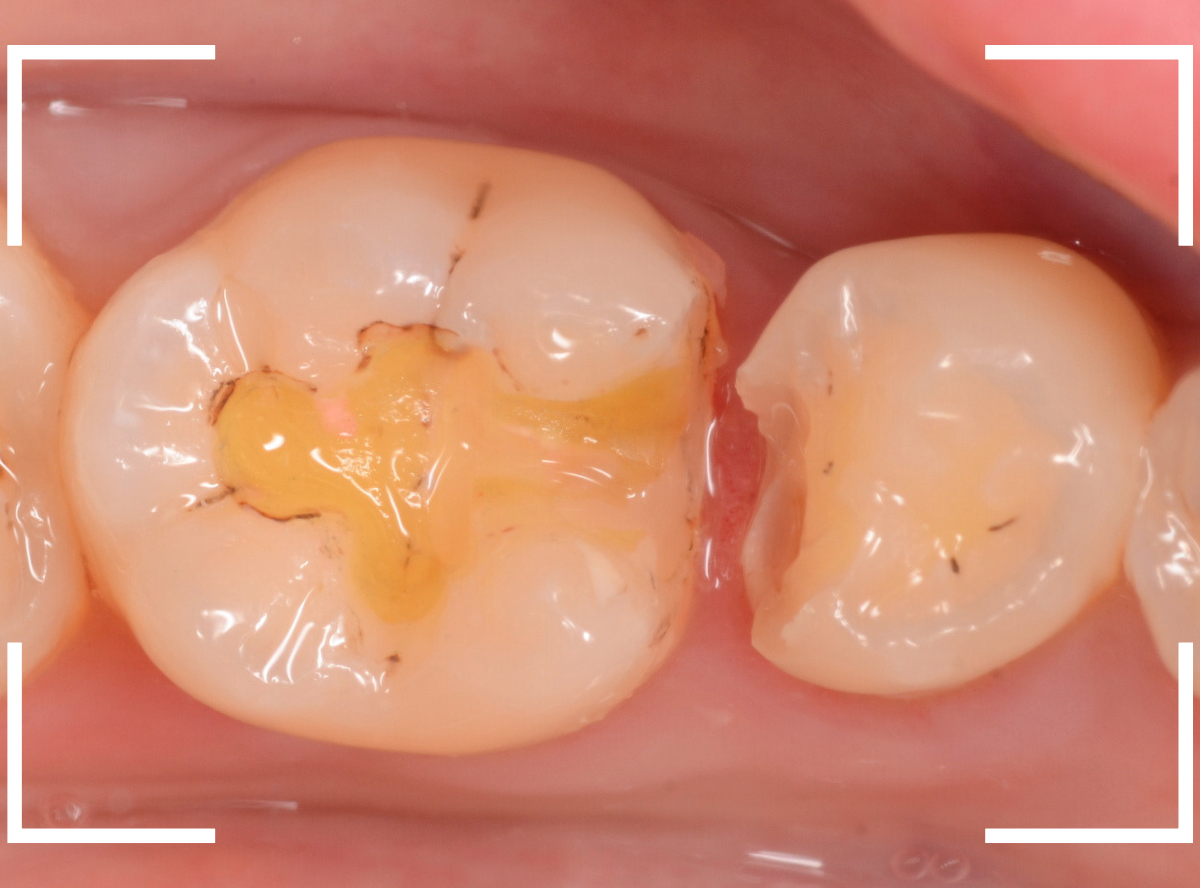

虫歯を全て除去しました。

幸い、あまり多く削る事なく進められたので良かったです。